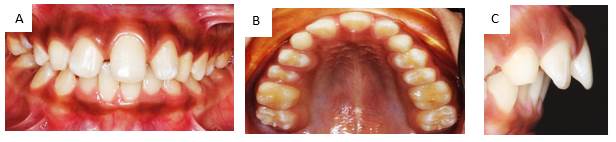

Paciente masculino de 10 años de edad, peso 23 Kg., estatura 123 cm., procedente de Jamundí, Valle del Cauca- Colombia. Asiste a consulta, en compañía de su tía, responsable del menor, quien refiere como motivo de consulta: “Mi sobrino tiene un solo diente adelante”. Al interrogatorio refiere: El niño es el segundo hijo de tres embarazos llevados a término; Antecedentes familiares, tía paterna padece diabetes, hipertensión y cáncer sin especificar. Antecedentes personales no reporta; la tía refiere que el niño, en la dentición decidua también presentó un solo incisivo central superior. Además, relata que sus otros dos hermanos presentan el mismo problema. Al examen extraoral se observa que la línea media no coincide con la punta de la nariz, ni con el centro del mentón; no presenta filtrum labial, el plano bipupilar no es paralelo a la línea comisural; existe incompetencia labial; orejas de tamaño, proyección e implantación aumentadas. (Figura 1) En el examen intraoral se observa un incisivo central único sobre la línea media del maxilar, ausencia de frenillo labial y papila incisiva, paladar oval y maloclusión clase II con proinclinación de incisivo central. (Figura 2 a, b y c).

Figura 1: Fotografía extraoral del paciente de frente donde se observa alteraciones a nivel de línea media y asimetría facial